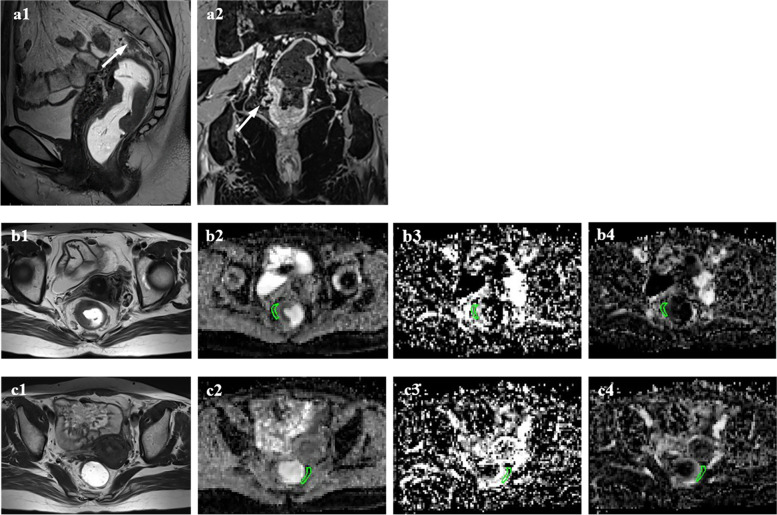

Fig. 4.

Measurement of IVIM parameters in the mesorectum in patients with positive mrEMVI. Sagittal T2-weighted imaging (a1) shows a tubular structure that contains a signal void (arrow). On coronal contrast-enhanced T1-weigheted imaging (a2), a small serpiginous vessel outside the tumour demonstrates an irregularly expanded contour (arrow). The ROIs in the MAT (b2 – b4) are located within 5 mm of the outline of the largest tumour segment, and the calculated IVIM parameters included D (1.45 × 10–3 mm2/s), D* (10.79 × 10–3 mm2/s), and f (0.15). The ROIs in the MDT (c2 – c4) are located contralateral to the tumour parenchyma as far as possible; D = 0.67 × 10–3 mm2/s, D* = 12.25 × 10–3 mm.2/s, and f = 0.34